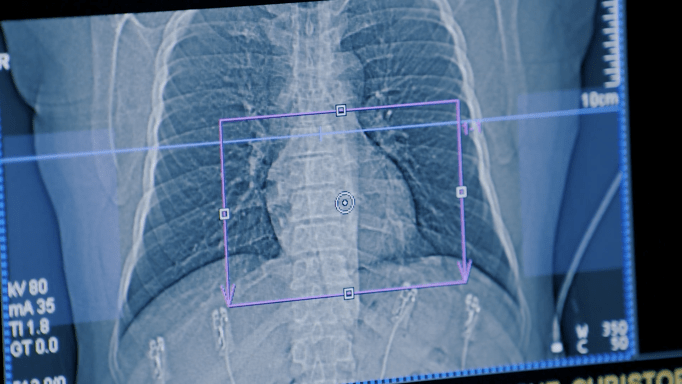

4 heart tests that diagnose heart conditions

Heart disease continues to be the leading cause of death in the U.S. for more than 100 years. Heart health mortality and disability rates are a stark reminder that cardiovascular imaging and screenings are a critical piece in detection and management of a multitude of heart conditions.